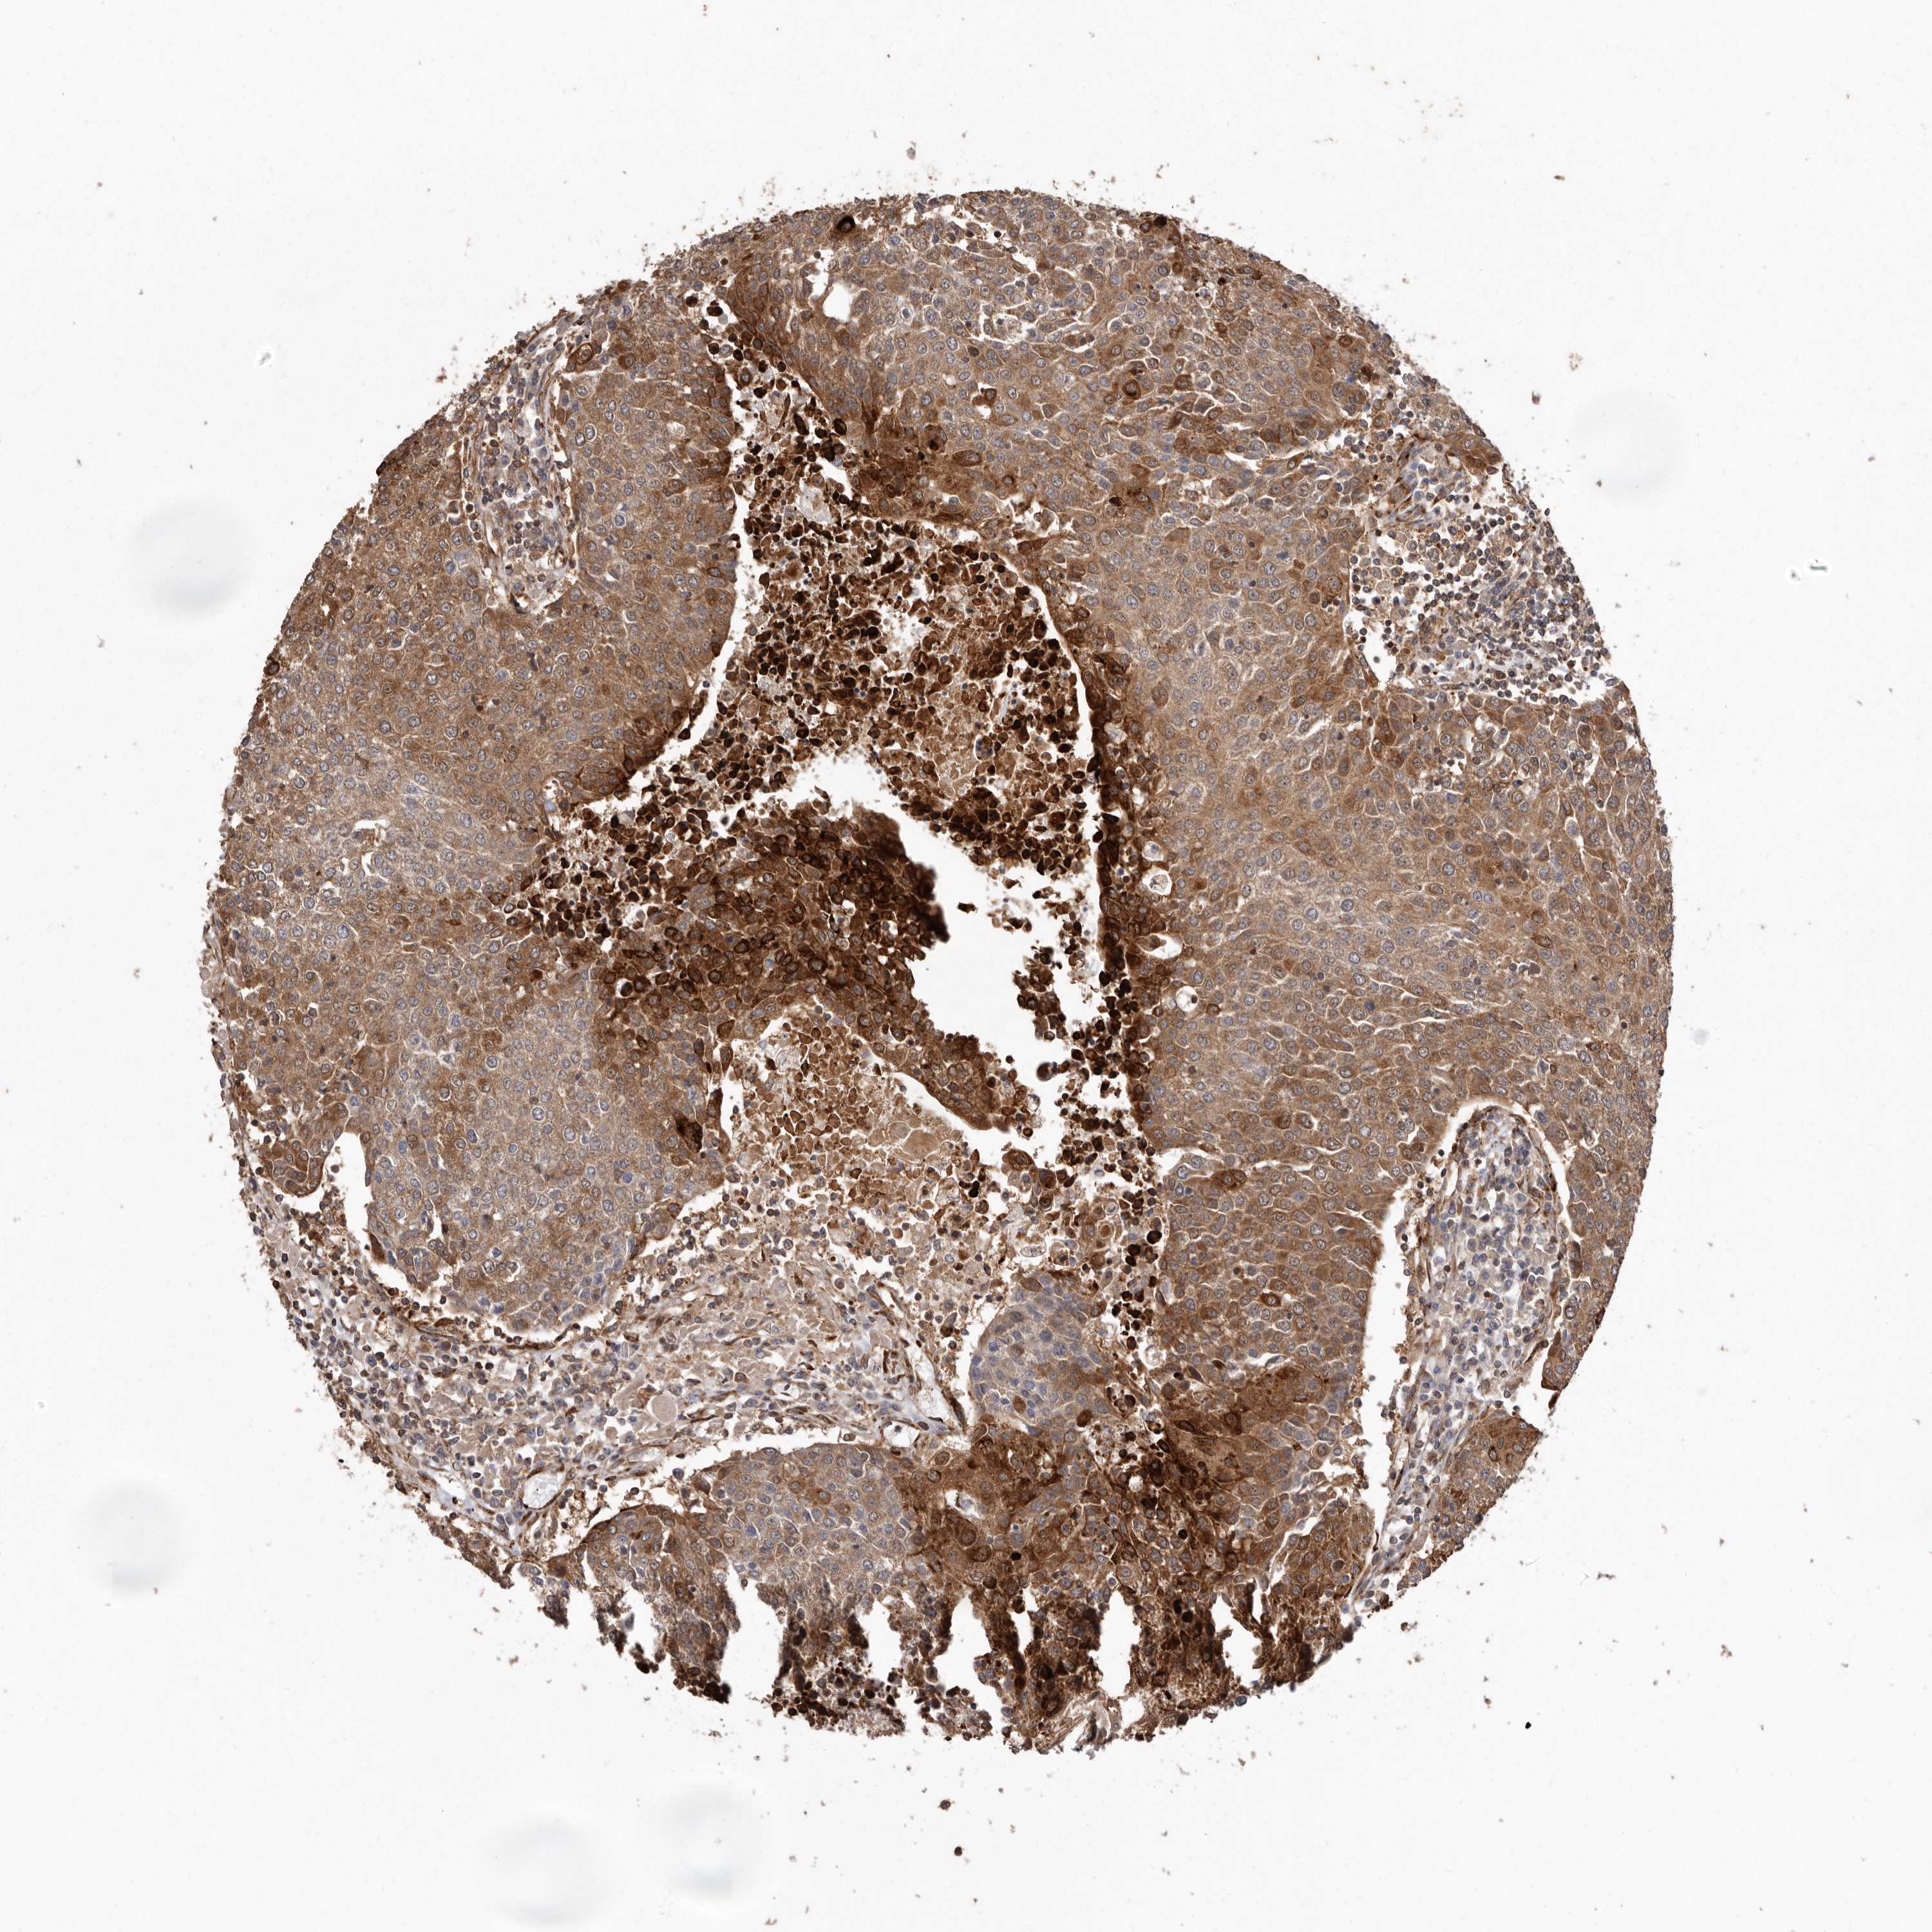

UROTHELIAL CANCER - Protein expressioni

A mouse-over function shows sample information and annotation data. Click on an image to view it in a full screen mode. Samples can be filtered based on level of antibody staining by selecting one or several of the following categories: high, medium, low and not detected. The assay and annotation is described here.

Note that samples used for immunohistochemistry by the Human Protein Atlas do not correspond to samples in the TCGA dataset.

Antibody stainingi

Antibody staining in the annotated cell types in the current human tissue is reported as not detected, low, medium, or high, based on conventional immunohistochemistry profiling in selected tissues. This score is based on the combination of the staining intensity and fraction of stained cells.

Each image is clickable and will lead to virtual microscopy that enables deeper exploration of all samples and also displays staining intensity scores, fraction scores and subcellular localization as well as patient and tissue information for each sample.

Antibody HPA028476

Antibody HPA028486

Antibody HPA028563

Staining

High

Medium

Low

Not detected

Intensity

Strong

Moderate

Weak

Negative

Quantity

>75%

75%-25%

<25%

None

Location

Nuclear

Cytoplasmic/membranous

Cytoplasmic/membranous,nuclear

Urothelial carcinoma, Low grade

Urothelial carcinoma, High grade